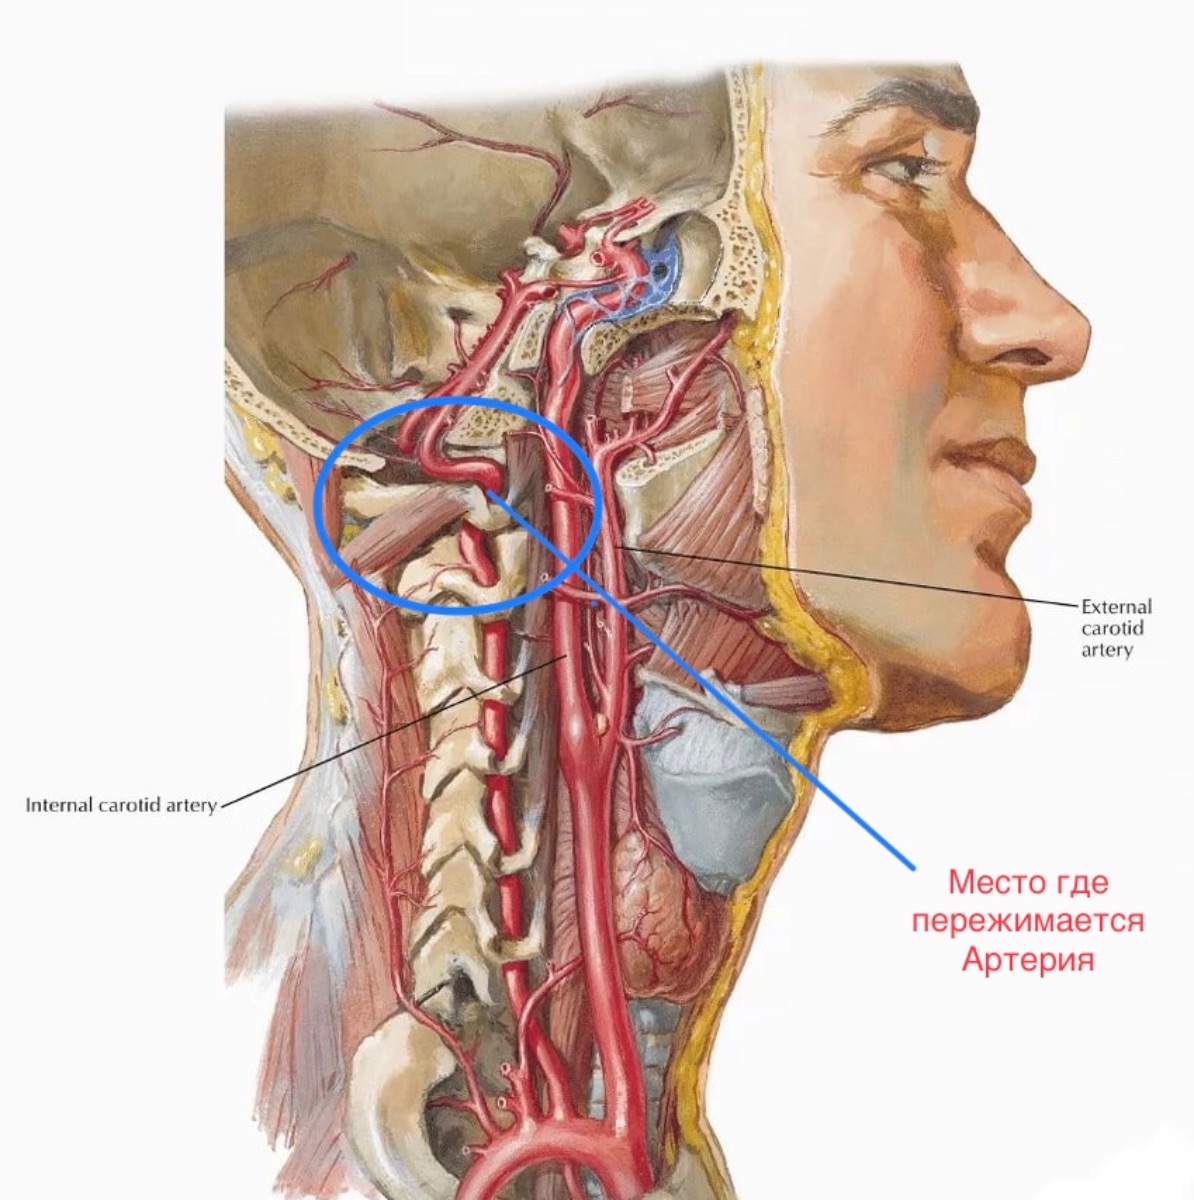

Анатомия внутренней яремной вены: КТ изображения